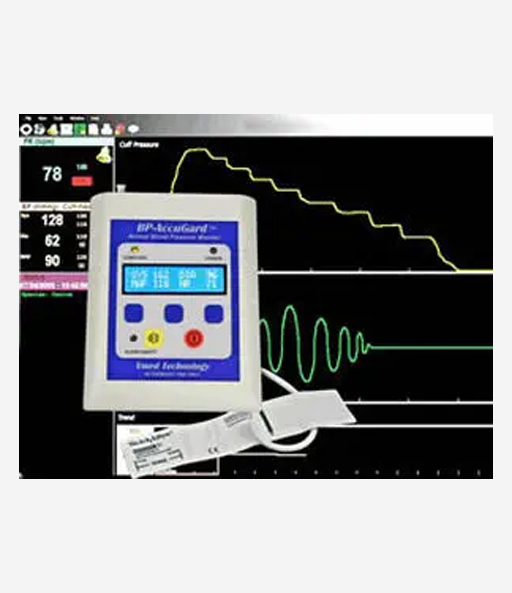

bp-accugard

Automatic Blood Pressure System